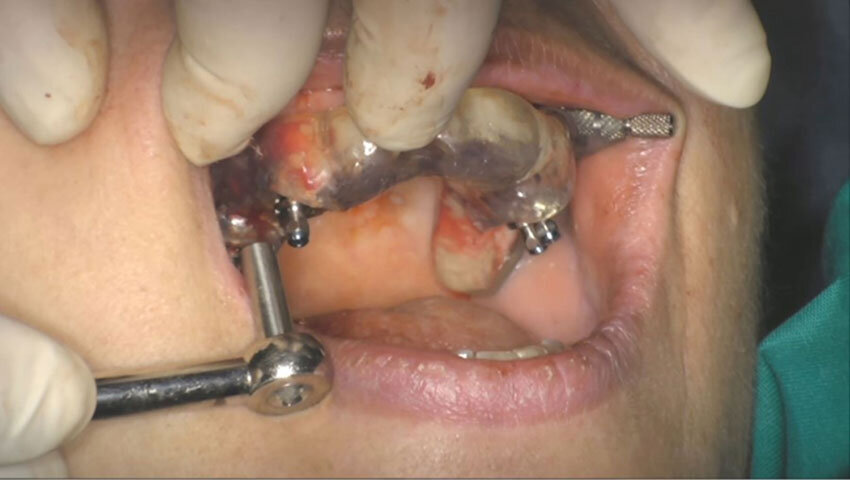

Figg. 1, 2_Situazione iniziale.

Figg. 45, 46_Implantologia chirurgica guidata.